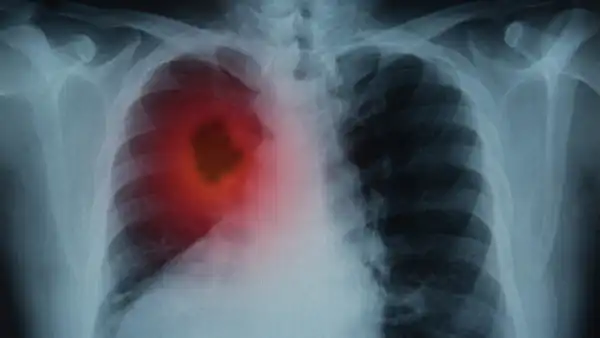

Рак легкого — одно из самых опасных онкологических заболеваний, однако существует надежный метод его диагностики — НДКТ-скрининг, который может спасти множество жизней. Об этом сообщил профессор и заслуженный врач Петр Яблонский в интервью.

"Без лечения медиана выживаемости у больных даже на первой стадии составляет всего около 16 месяцев. А у нас, согласно официальным данным, 43 процента новых случаев выявляются уже на четвертой стадии," — отметил главный торакальный хирург Минздрава России.

Профессор Яблонский подчеркивает, что медицинское сообщество активно поддерживает внедрение скрининга с использованием низкодозной компьютерной томографии (КТ). Раннее выявление рака легкого на первой стадии значительно увеличивает пятилетнюю выживаемость пациентов, которая составляет от 92 до 98 процентов.

Профессор также напоминает, что положительное влияние скрининга было доказано еще в 1990-х годах. В то время проведенные исследования показали, что среди курильщиков старше 50 лет смертность от рака легкого снизилась на 25 процентов благодаря раннему выявлению.

Более поздние исследования подтвердили еще более высокую эффективность НДКТ-скрининга, продемонстрировав снижение смертности вдвое.